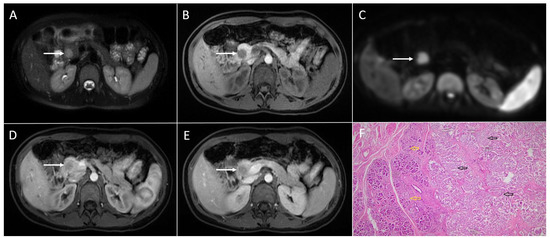

3.2. Pancreatic Adenocarcinoma

3.4. Pancreatic Metastases